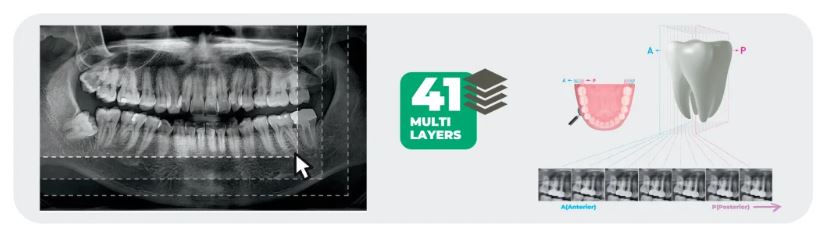

- 41-layers Panoramic images: Insight Pan

Insight 2.0

The Insight Pan is capable of taking a multilayered panoramic image, called an Insight Pan, which provides a unique in-depth look across a single focal trough. Insight 2.0 has an upgraded free FOV feature so you will be able to capture just the area of interest.